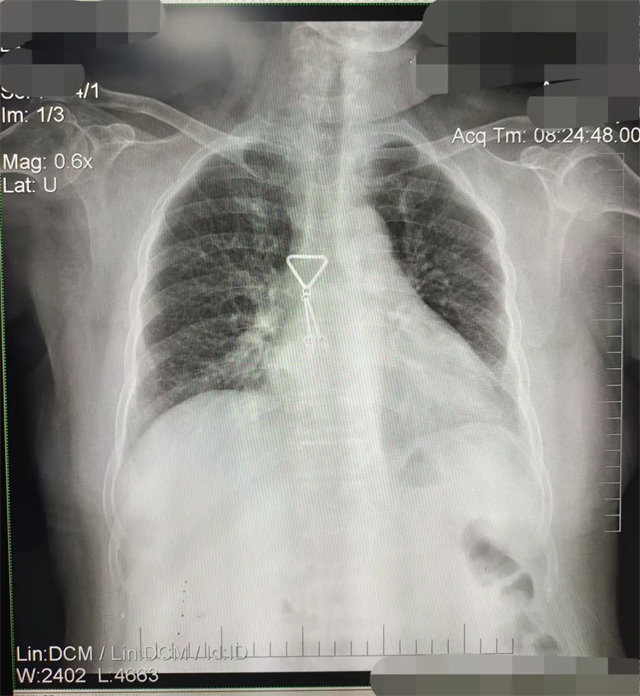

拍攝的不合格胸片的缺陷和解決方法

缺陷:兩肩胛骨未拉開肺野之外,吸氣不完全,且存在金屬飾品遮擋。

解決:去除金屬飾品及內(nèi)衣后重新按標(biāo)準(zhǔn)體位攝片即可。